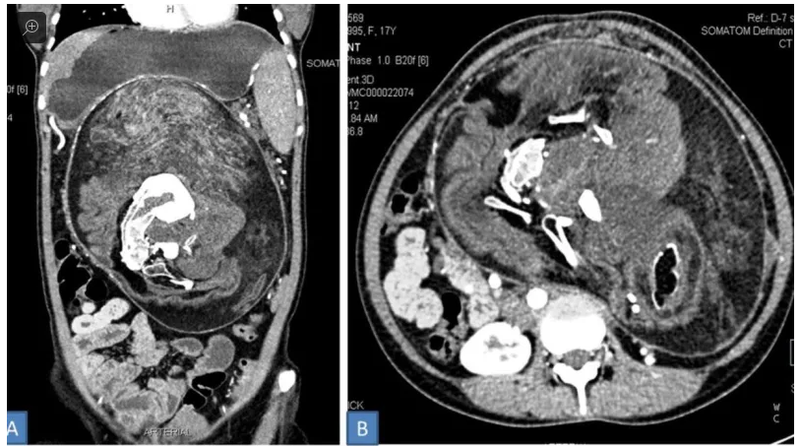

Đối với ngươì̀ phụ nữ Ấn Độ này, các bác sĩ đã phát hiện ra điểm bất thường cách đây 5 năm khi cô đến khám. Cả cô gái và gia đình nhận thấy cô có một khối u rất cứng ở trong bụng. Trong 5 năm tiếp theo, kích cỡ khối u tăng dần khiến cô gái này đau đớn thường xuyên. Vào thời điểm phát hiện ra, “quái thai” này đã “sống” ở trong bụng cô gái 17 năm, cô thậm chí không thể ăn nhiều vì luôn cảm thấy no, rất có thể do khối u đã lan sang các cơ quan nội tạng của cô.

Sau quá trình kiểm tra ban đầu, các bác sĩ vẫn nghi ngờ đây chỉ là một khối u. Sự thật khủng khiếp chỉ được phát hiện ra khi họ tiến hành chụp ảnh CT scan vùng bụng cô gái và tìm thấy những mảnh xương giống như hình dạng đốt sống, xương sườn. Các bác sĩ đã tiến hành phẫu thuật và loại bỏ nó.

Theo báo cáo, khối “quái thai” này có tóc, xương và một số bộ phận cơ thể khác như răng và cấu trúc giống như các chi. Trong lịch sử các dị tật “bào thai trong bào thai”, đây là trường hợp lớn nhất từng được phát hiện.